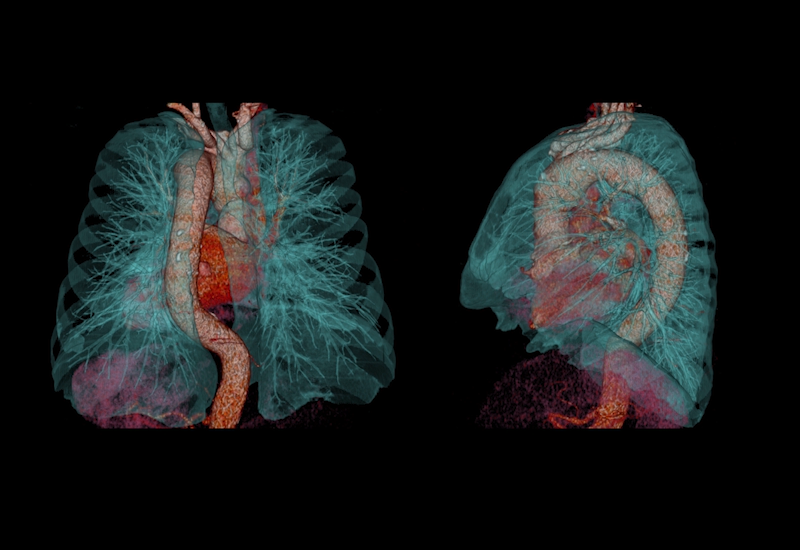

Упрощенная генерация 3D изображений

Технологии Aquilion Lightning позволяют создавать объемные изображения с исключительной простотой. Одним нажатием кнопки осуществляется выбор необходимого протокола, что позволяет моментально вывести на экран нужные изображения.